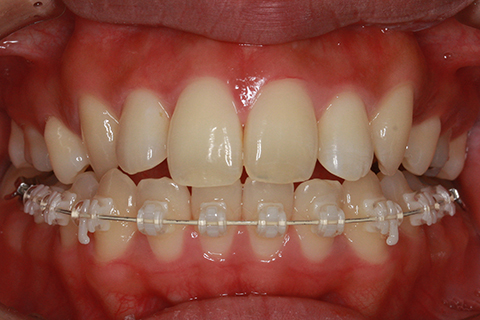

ハーフリンガル矯正2:上の歯のみ舌側矯正で治療(矯正期間18ヶ月)

- 年齢・性別

- 23歳女性

- 治療期間

- 1年6ヶ月

- 抜歯

- 上顎4番

- 治療費

- 110万円(税込み)

- ハーフリンガル矯正

- 治療内容

- 上下前歯部凸凹の改善

- 施術の副作用(リスク)

- 裏側矯正の特性上、表側矯正と比較すると治療期間が長くかかる場合が多い。